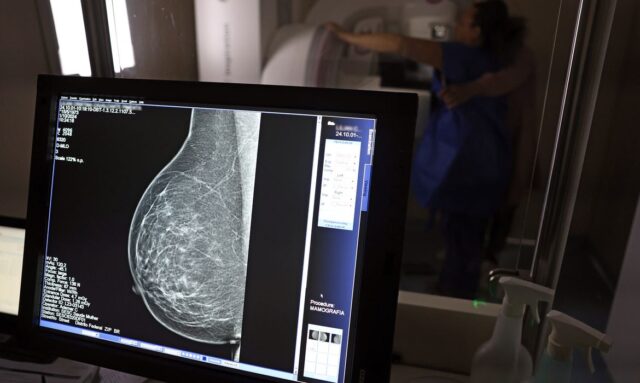

No mês de conscientização sobre o câncer de mama, um relatório destaca a importância de acesso igualitário ao rastreamento e tratamento da doença. Segundo o Atlas da Radiologia no Brasil, do Colégio Brasileiro de Radiologia e Diagnóstico por Imagem (CBR), o acesso aos mamógrafos ainda é um desafio.

O país tem 6.826 equipamentos registrados, sendo 96% em funcionamento. Metade deles está disponível no Sistema Único de Saúde (SUS), responsável por atender 75% da população. Isso equivale a 2,13 mamógrafos por 100 mil habitantes dependentes do SUS.

O Brasil tem uma cobertura muito baixa de mamografias: 24%. O ideal recomendado pela Organização Mundial da Saúde é de 70%. Mesmo em lugares como o estado de São Paulo, que tem a maior concentração de mamógrafos do país, a taxa gira em torno de 26%.

Em setembro, o Ministério da Saúde ampliou as diretrizes de rastreamento, recomendando que mulheres entre 40 e 49 anos realizem mamografias, mesmo sem sintomas. De acordo com o Instituto Nacional do Câncer (Imca), mais de 73 mil mulheres recebem o diagnóstico de câncer de mama anualmente no Brasil.

“O que é efetivo na redução da mortalidade é você descobrir o tumor antes de ter sintoma clínico. Quanto menor o tumor, melhor para a gente descobrir o tratamento e maior a chance de cura. E a gente só consegue fazer isso com exames de imagem”, diz Ivie.

Ela explica que no caso de diagnóstico de um câncer de mama com menos de 1 cm, a chance de cura é de 95% em cinco anos, independentemente se ele é do tipo mais agressivo. “E esses tumores só vão ser detectados na mamografia. Essas pessoas que têm que ir fazer mamografia são mulheres saudáveis. Não são mulheres doentes”, acrescenta.